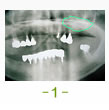

症例1 2007 9/14 更新

治療前 治療完了

治療前

平成16年7月7日

治療完了

平成19年5月1日

(治療期間:2年10ヶ月)